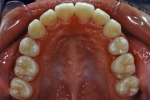

初診時